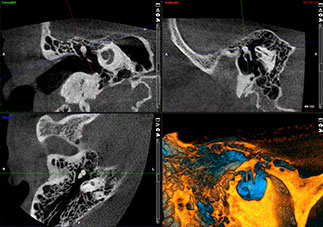

高度なENTイメージング

プランメカ ProMax 3D Plusデバイスのボクセルサイズは75~600 μmの範囲ですが、プランメカ Romexis® ソフトウェアは、気道、副鼻腔、軟組織、および耳の最も小さな骨構造も画像化する多用途の機能を搭載しております。